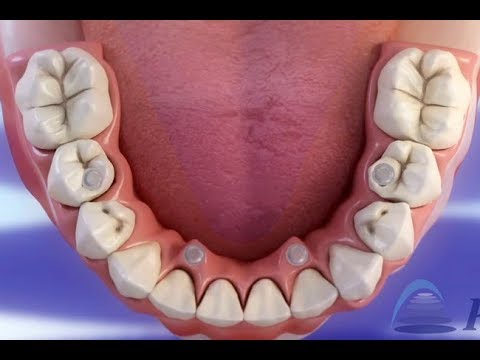

歯科矯正の種類 ©

歯列矯正 – 要素とその役割 ©